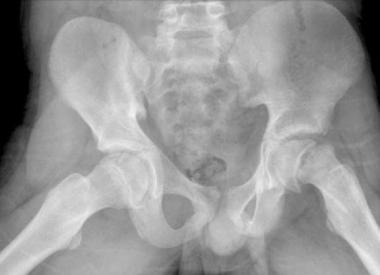

Chụp X-quang